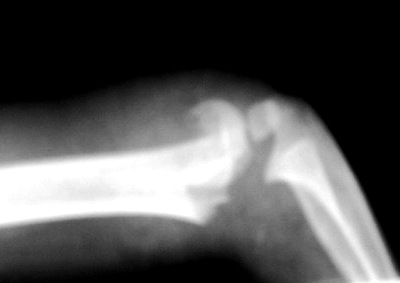

62. Травма голени

Случай №1 Футболсит пришёл на приём после травматолога. Сделали снимок. Случай №2 И другой футболист.